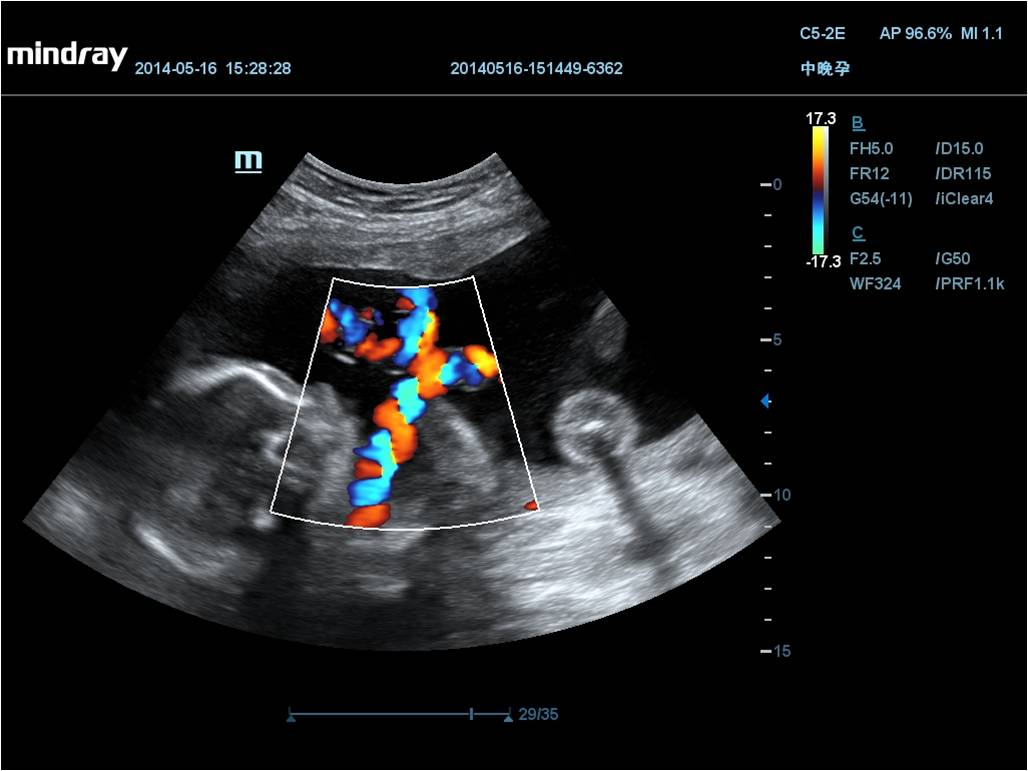

Mindray DC-70 Exp с технологией X-Insight – это узи-аппарат для высококачественной диагностики. Преимущества: высокая эффективность, точность визуализации, результат в «одно касание» с экспертными датчиками. Рекомендуется для государственных учреждений.